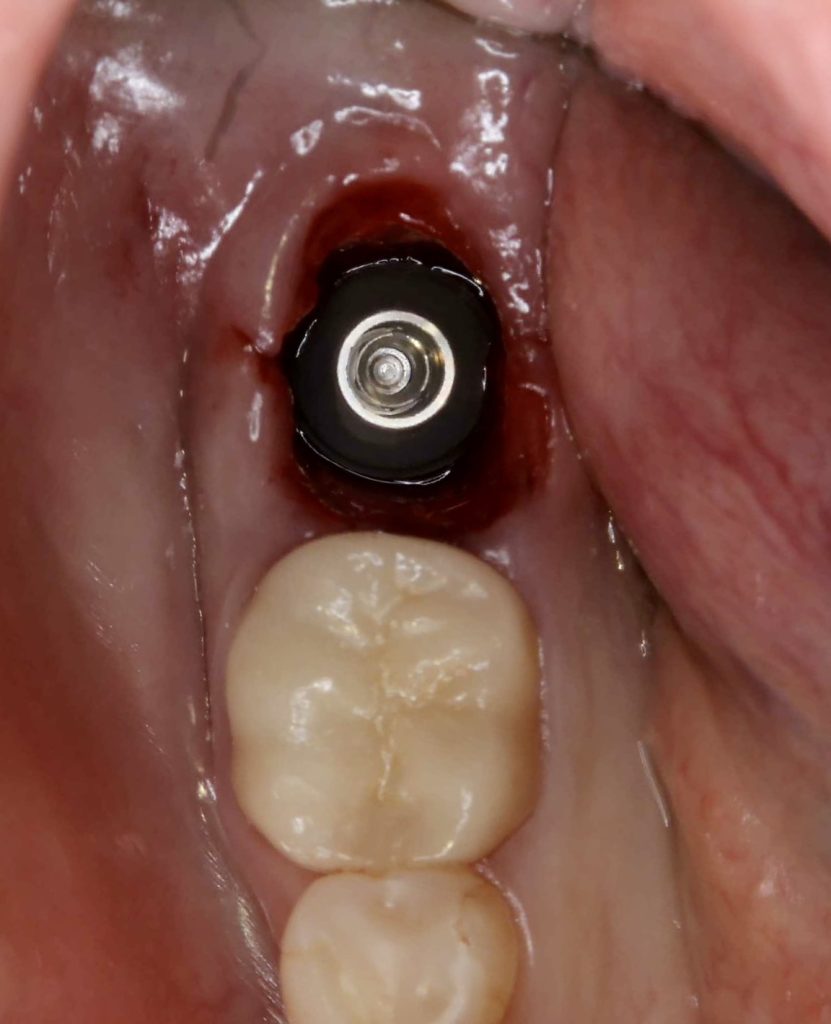

30代、女性、右下に違和感があることを健診中に申され、インプラント治療を行いました。

| 診断結果 | 右下7番歯根破折 |

| 治療内容 | 抜歯即時インプラント |